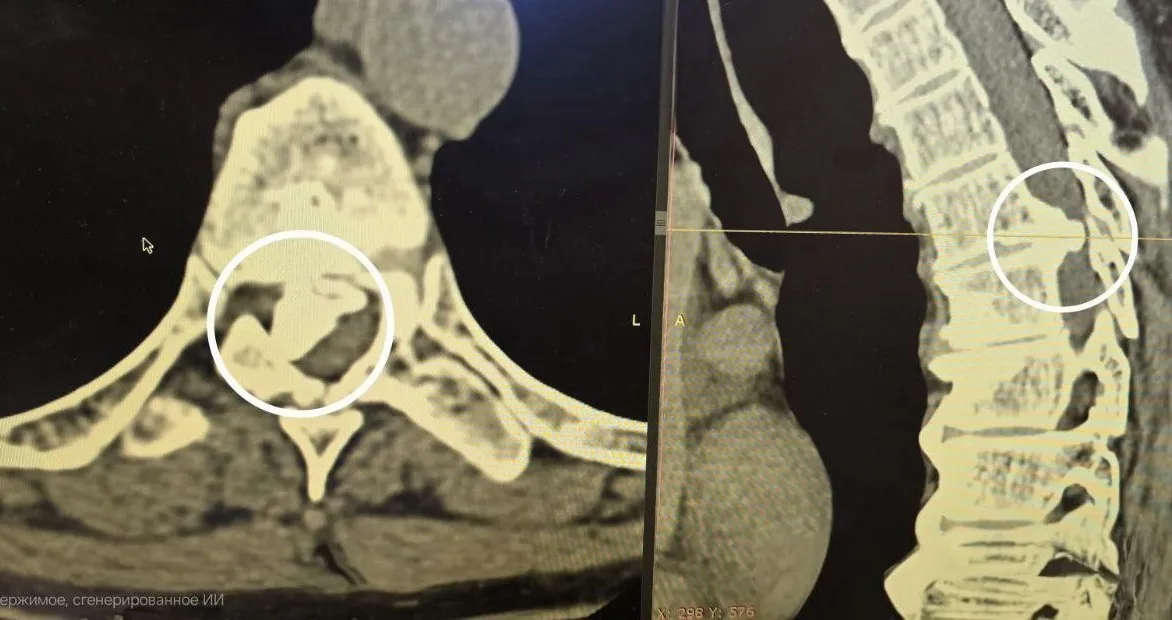

Нейрохирурги помогли 64-летней женщине избавиться от огромной грыжи позвоночникаВ подмосковном медучреждении врачи провели сложную нейрохирургическую операцию, в результате которой 64-летней пациентке вернули способность ходить. Женщина обратилась в больницу с жалобами на слабость в ногах и боли в спине. В ходе обследования врачи диагностировали огромную межпозвонковую грыжу, которая сдавливала спинной мозг. Об этом сообщает Министерство здравоохранения Московской области.

По словам заведующего отделением нейрохирургии Павла Савинкова, грыжа была настолько твердой, что ее текстура напоминала камень. Она проросла в спинномозговой канал, почти полностью перекрыв нервные проводники. Операция длилась несколько часов, и хирургам пришлось использовать алмазный бор, чтобы аккуратно удалить грыжу.